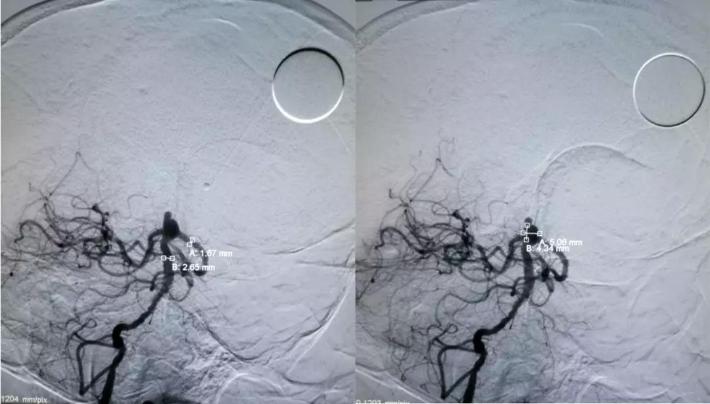

拟通过微导丝将支架微导管预置到右侧大脑后动脉,但微导丝支撑力不足,直接通过基底动脉至右侧大脑后动脉较困难,先在动脉瘤腔内部分填塞弹簧圈(4mm*10cm),以作支撑,再将微导丝带微导管置入右侧大脑后动脉,经微导管送入LEO支架(2.5*18mm)

采用支架半释放技术,LEO 2.5*18mm半释放,继续送入编框圈编框成篮,再依次填入填充圈

采用支架推挤技术,推挤支架,保护双侧大脑后动脉、右侧小脑上动脉,继续将动脉瘤填塞致密,完全打开支架

处理右侧颈内动脉虹吸段夹层动脉瘤。

预置入支架导管,栓塞动脉瘤用微导管头端超选进入动脉瘤腔,通过支架导管送入Enterprise支架(4.5*22mm)并打开支架,填入弹簧圈栓塞夹层动脉瘤。但此时发现大脑前动脉A1段不显影。